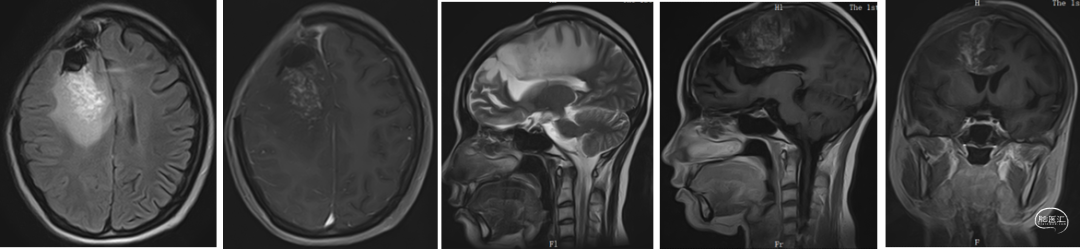

2020.2.10MRI基线